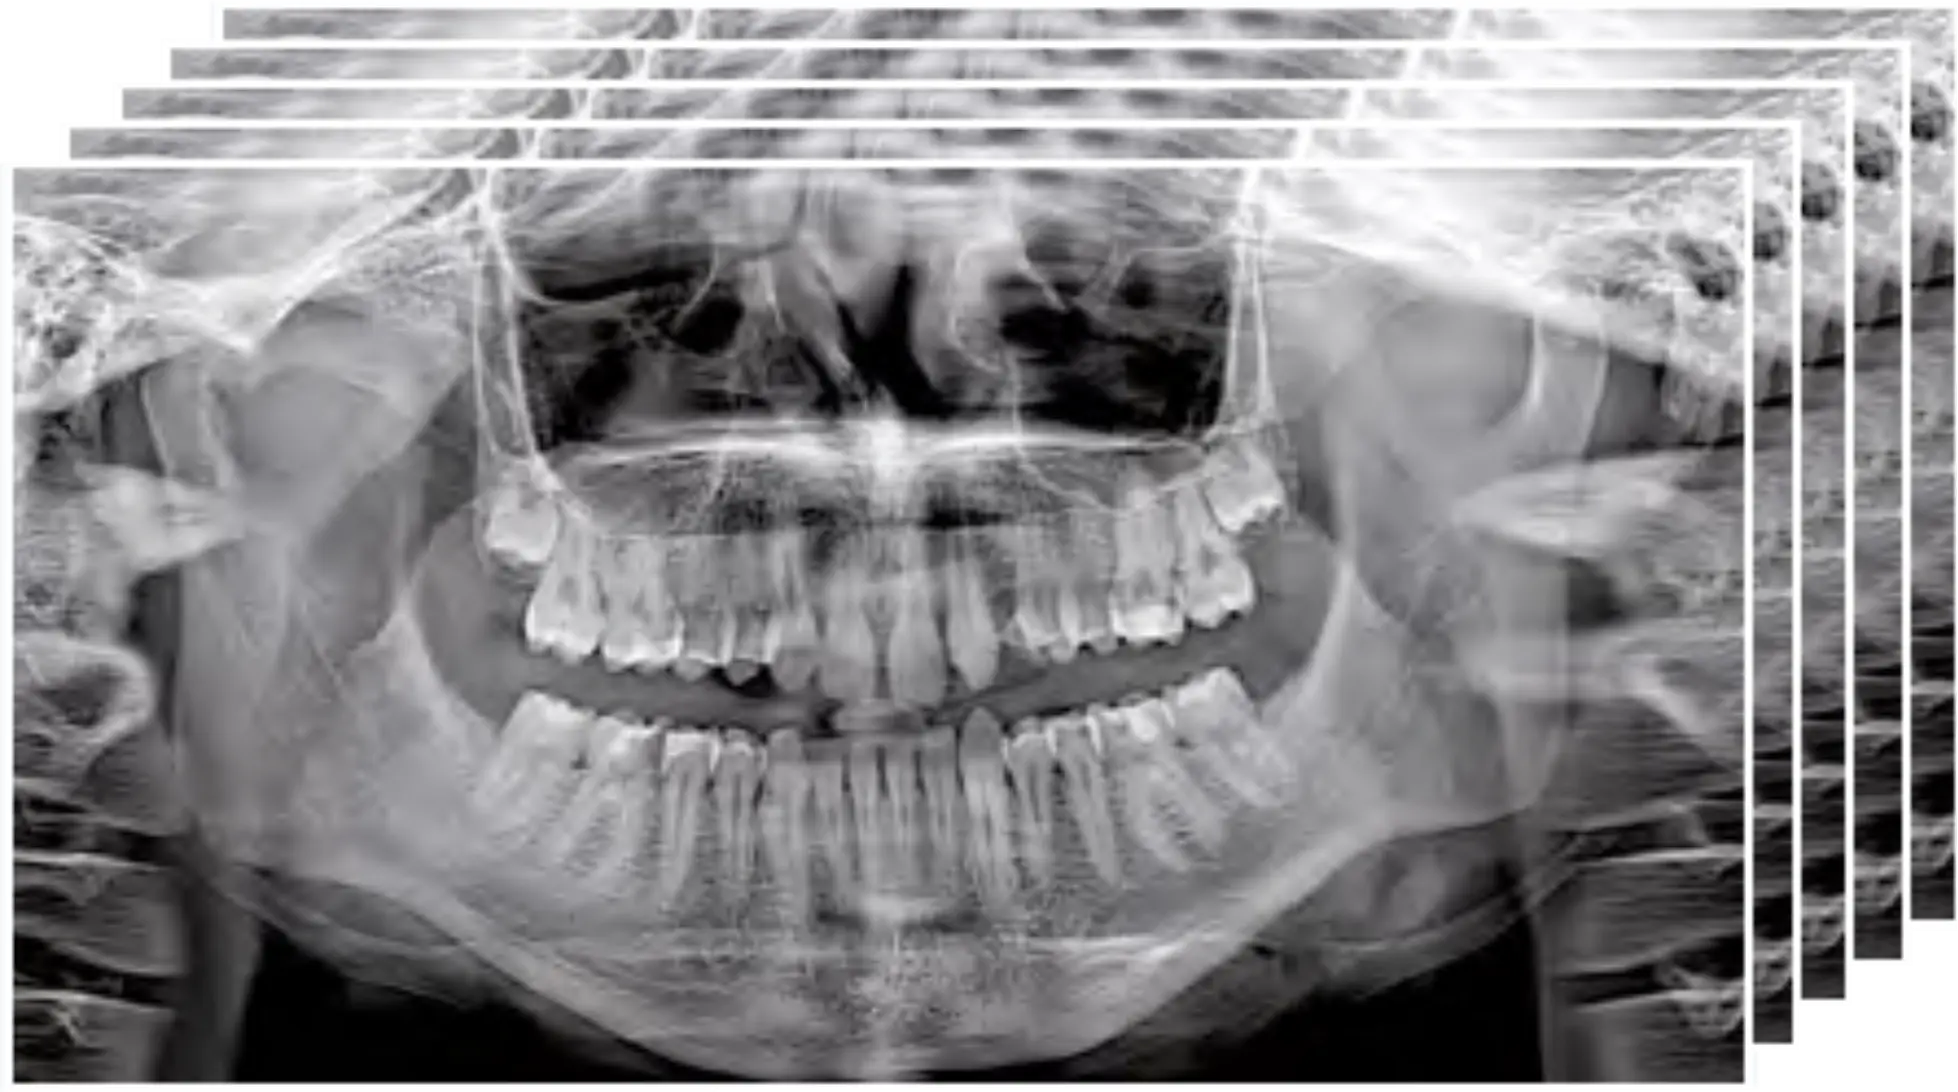

MultiPan can create a set of five different panoramic images with one scan, so the user can choose the most-suitable view. This function is particularly useful when examining complex morphologies.